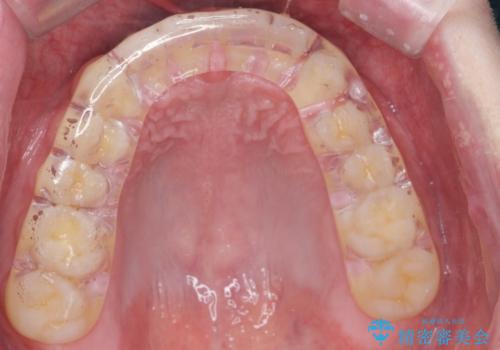

ナイトガードで歯の予防をしたい。

- 歯軋りが気になるとの事で来院。

歯が割れたりするのを予防したいとの事でしたのでナイトガードを作製しました。

- 自費ナイトガード 3.3万円費用は治療当時の料金となります

ナイトガードを使用することにより歯が割れるリスクが低くなります。